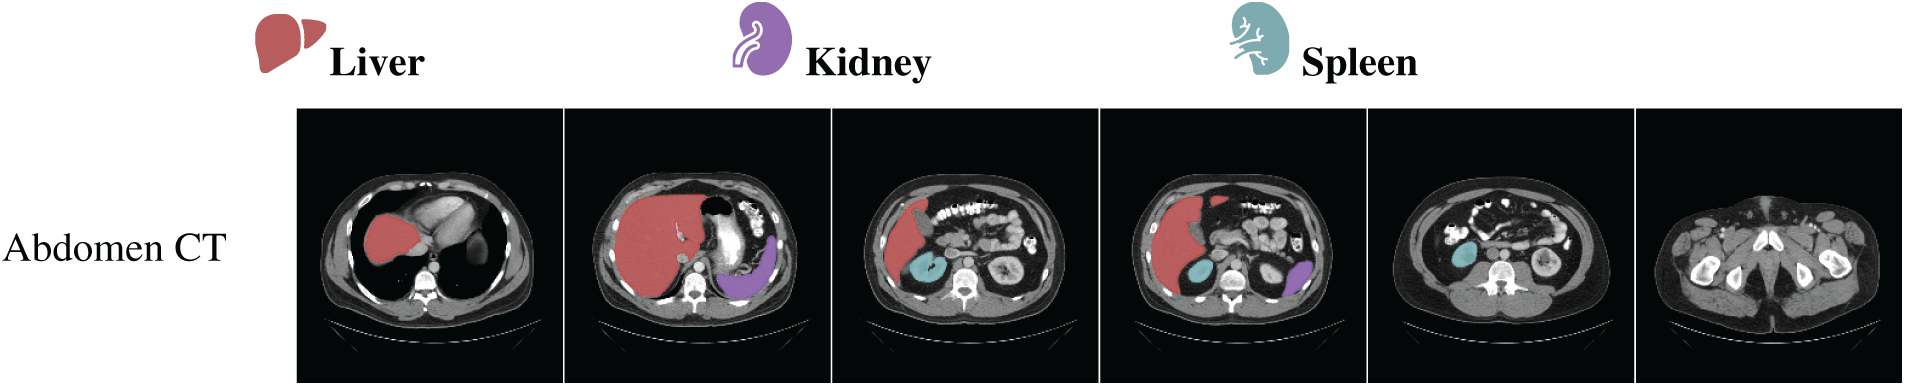

To evaluate the segmentation performance of different models across various anatomical structures in [112], Dice similarity coefficient distributions are analyzed based on organ and model types. The boxplot in Fig. 3 illustrates the organ-wise variability in segmentation accuracy for the models, i.e., SAM and MedSAM, applied to abdominal CT images. Overall, the aorta and liver exhibited higher median Dice scores, indicating relatively consistent and accurate segmentation across slices, whereas the kidneys and spleen showed greater interquartile spread and lower median performance. This variability may reflect challenges associated with organ boundary delineation, anatomical variability, or contrast heterogeneity. Notably, both models demonstrated competitive performances across most organs, suggesting robust generalization in multi-organ segmentation tasks. These findings underscore the importance of organ-specific evaluation when benchmarking segmentation models and highlight potential areas for improvement in anatomical precision, particularly for smaller or morphologically complex structures.

Figure 3: Organ-wise distribution of Dice similarity coefficients for different semantic segmentation models, i.e., SAM and MedSAM. Boxplots illustrate the variability in segmentation accuracy across spleen, kidneys (right and left), liver, and aorta